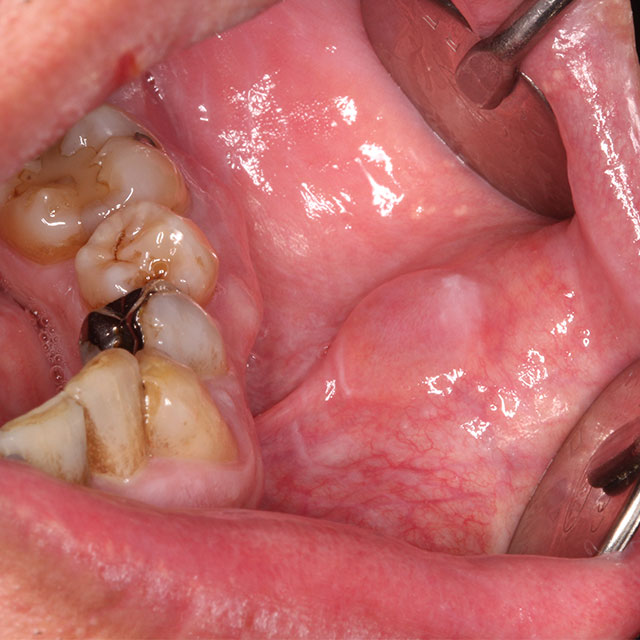

奥歯の一番奥にある歯を親知らず(智歯)といいます。現代人は顎の大きさが小さくなったこともあり、この親知らずが正常に生えないことが多く、まったく生えないか半分埋まった状態になっていることがあります。この状態では親知らずに歯ブラシが十分届かず、汚れが溜まって炎症を引き起こします(智歯周囲炎といいます)。そのような状態になると痛みと腫れが出るので、抗菌薬と痛み止めの薬で炎症をおさめますが、何度も炎症を繰り返すことが多いです。炎症を起こした親知らずは抜歯が最適な根本治療になります。